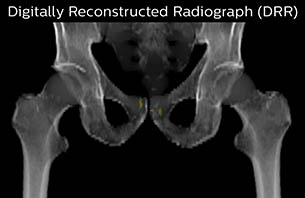

Using the mDIXON and 3D bFFE images, the RT planner marks the position of the nickel-titanium fiducial markers, and contours are transferred to the digitally reconstructed radiographs (DRRs). Reference image matching is based on these markers. “In the rare cases, where visualization of the fiducial markers fails, we do a CT to confirm their location,” Dr. Keyriläinen notes.

MR-only simulation workflow The 3D T1W FFE mDIXON sequence provides in-phase, water and fat images in one acquisition. Target and organs-at-risk are delineated on the 3D T2W TSE images. Prostate GTV is shown in orange, PTV in purple. The 3D bFFE sequence is used by the planner to mark the position of the fiducial markers (gold anchors) and contours are transferred to the digitally reconstructed radiographs (DRRs).